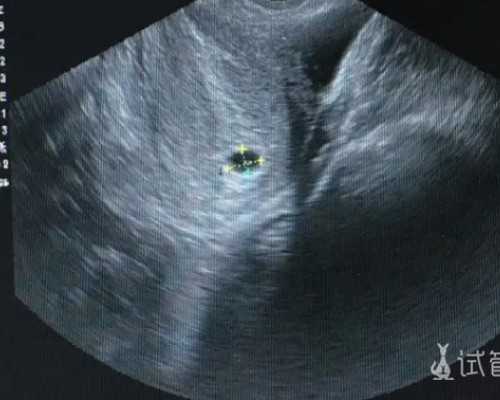

在国内进行试管手术,已经成为许多不孕不育患者都会选择的方式了,虽然很多人对于试管婴儿手术仍然存在着诸多偏见,但是已经更加成熟完善的试管技术,当然能够给人们带来更多的惊喜,也可以帮助大家实现生育的梦想。全国试管医院最好究竟是哪家呢?我们在了解的过程中,会发现这是很多人都疑惑的问题,是否能够弄清楚什么医院更值得选择呢?不断掌握到更多的情况,就会知道接下来该做什么了。

以上关于全国试管医院最好的相关介绍,对朋友们当然会有一定的帮助作用,也能够更迅速的做出选择了。通过三代试管手术生出龙凤胎,是很多朋友都有的打算,但是这样的说法是真的吗?询问过医生,或者掌握到更多情况以后,我们就能确定并不是这么一回事了,不管是几代手术,都不能保证百分百生出龙凤胎或者双胞胎。

很多朋友明明身体健康,可是却一直无法成功受孕,精子或者卵子的质量好坏,才是根本所在,试管手术之所以能够越来越受认可,就是因为可以更好的解决这类问题。为了保证卵子质量和数量达到手术标准,建议大家在术前和术后认真调理身体,保持着较好的状态。